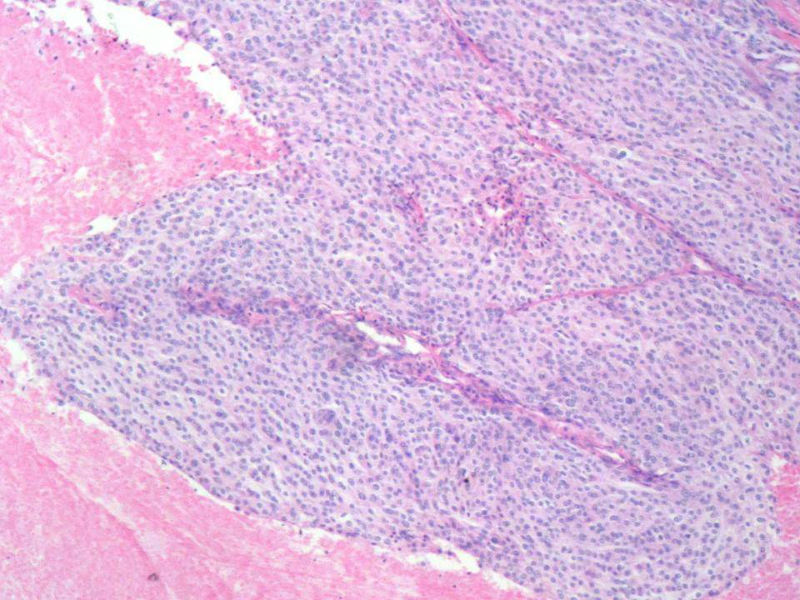

肿瘤性坏死本身是凝固性的一种类型,特点是细胞坏死,但组织轮廓仍存在。其坏死组织是肿瘤成分。

普通的凝固性坏死一般是由血栓栓塞引起的,梗死灶与周围正常组织之间都有炎性充血带。

这是我们科室最近遇到的一例肿瘤,所发生的肿瘤性坏死。

描述:肾梗死镜3a